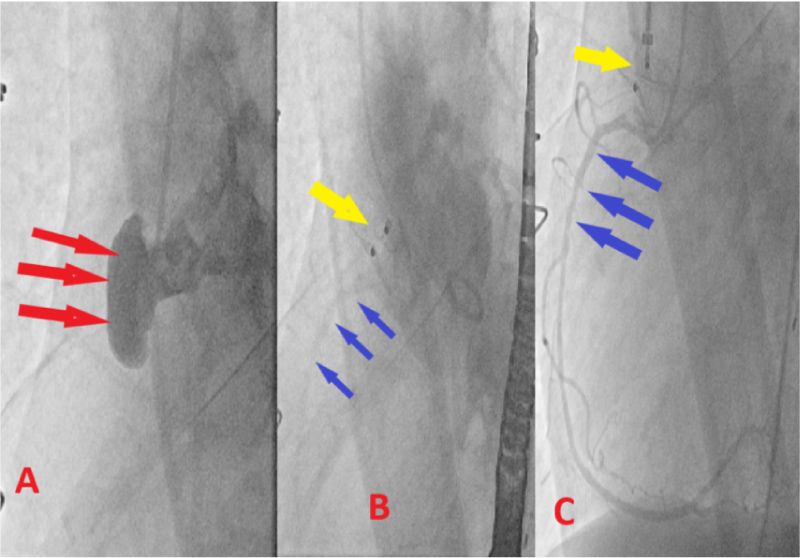

After a rigorous Structural team review, we had an open discussion with the patient and her family. She understood that this was an off-label procedure and wished to proceed. We accessed the patient's bilateral common femoral arteries using a modified Seldinger technique under fluoroscopic and ultrasound guidance. An 8-French sheath was placed on the right groin, and a 5-French sheath was placed on the left groin. A 9 -French left femoral venous sheath was also placed using modified Seldinger technique in the anticipation of requiring intracardiac echocardiography. The patient was anticoagulated with systemic heparin. We kept the activated clotting time between 250 and 300 throughout the entire case. The intracardiac echocardiogram probe was advanced, and baseline images were taken. The images were not optimal, so we decided to switch to transesophageal echocardiogram (TEE) imaging. A Judkins R4 catheter was used to engage the pseudoaneurysm and angiography was performed. Fortunately, the Judkins R4 catheter engaged the pseudoaneurysm well. We used the heat gun to shape the 8-French TorqVue™ delivery catheter (Abbott Laboratories) to seat well. We choose a 12 mm Amplatzer ventricular septal defect occluder, as the outer disc diameter was 4 mm on each side of the occluder waist. This was done to avoid right coronary occlusion. Under transesophageal echocardiography and fluoroscopic guidance, the 12 mm Amplatzer muscular ventricular septal defect occluder was deployed in good position. Right coronary angiography was performed to ensure that there was no occlusion. The right coronary was patent and was easily engageable. There was no evidence of compromise of the RCA ostium, which was located in close proximity to the inferior margin of the device. Aortic root angiography was performed with a pigtail catheter that showed appropriate closure of the pseudoaneurysm, and there was no evidence of contrast reflux from the pseudoaneurysm to the aorta (Figure 3A, Figure 3B and Figure 3C). The aortic valve was intact without any compromise of leaflet mobility. The following morning, the patient underwent TEE that demonstrated a well seated plug and normal aortic valve functioning.

Figure 3: A) Red arrows: Demonstrating intraoperative angiography of the AAP; B) Yellow arrow: Demonstrating well seated occluder device; Blue arrows: Patent RCA; C) Selective engagement of the RCA, while occluder is in place. View Figure 3